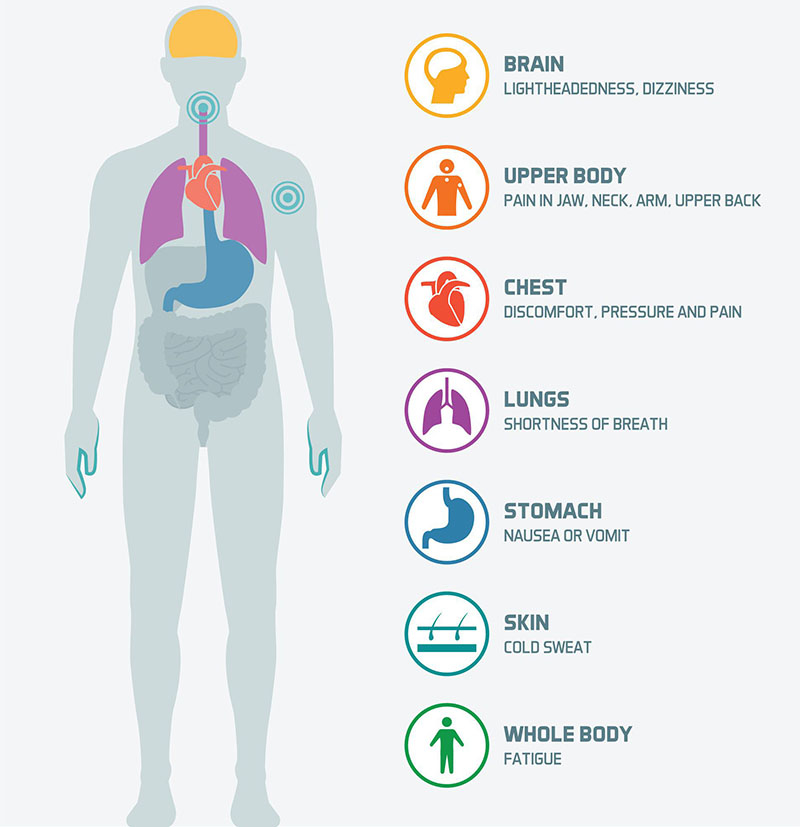

When You Feel #ChestProblem in Long Time and You Treated Many Types of …

Pressure On Chest

Pictures Of Chest